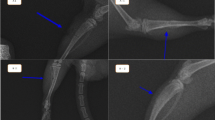

Nine rabbits were divided into three groups for femoral ablation, exposing the growth plate to different temperatures (T1 = 43–45 °C; T2 = 46–48 °C; T3 = 49–51 °C). After 5 weeks, the changes in the femurs were assessed by macroscopic images, micro-CT, haematoxylin and eosin staining, and immunohistochemistry of Col2a1 (type II collagen). At the cellular level, rabbit epiphyseal chondrocytes were exposed to 37 °C, 44 °C, 47 °C and 50 °C for 5 min. Then, proliferation and chondrogenic differentiation were detected.

The rabbits in the T2 and T3 groups developed length discrepancies and axial deviations of femurs, abnormal newly formed bone in the marrow cavity, disorganized growth plates and decreased Col2a1 expression. At the cellular level, the cells exposed to 47 °C and 50 °C for 5 min showed decreased viability, increased apoptosis, decreased extracellular matrix synthesis and decreased matrix mineralization. However, the changes in rabbits in the T1 group and cells at 44 °C did not show a significant difference.

The ablation of growth plates at temperatures above 45 °C for 5 min results in decreased chondrocyte viability and disorganized growth plates, leading to growth disturbances. Further studies are warranted to confirm these promising initial results.